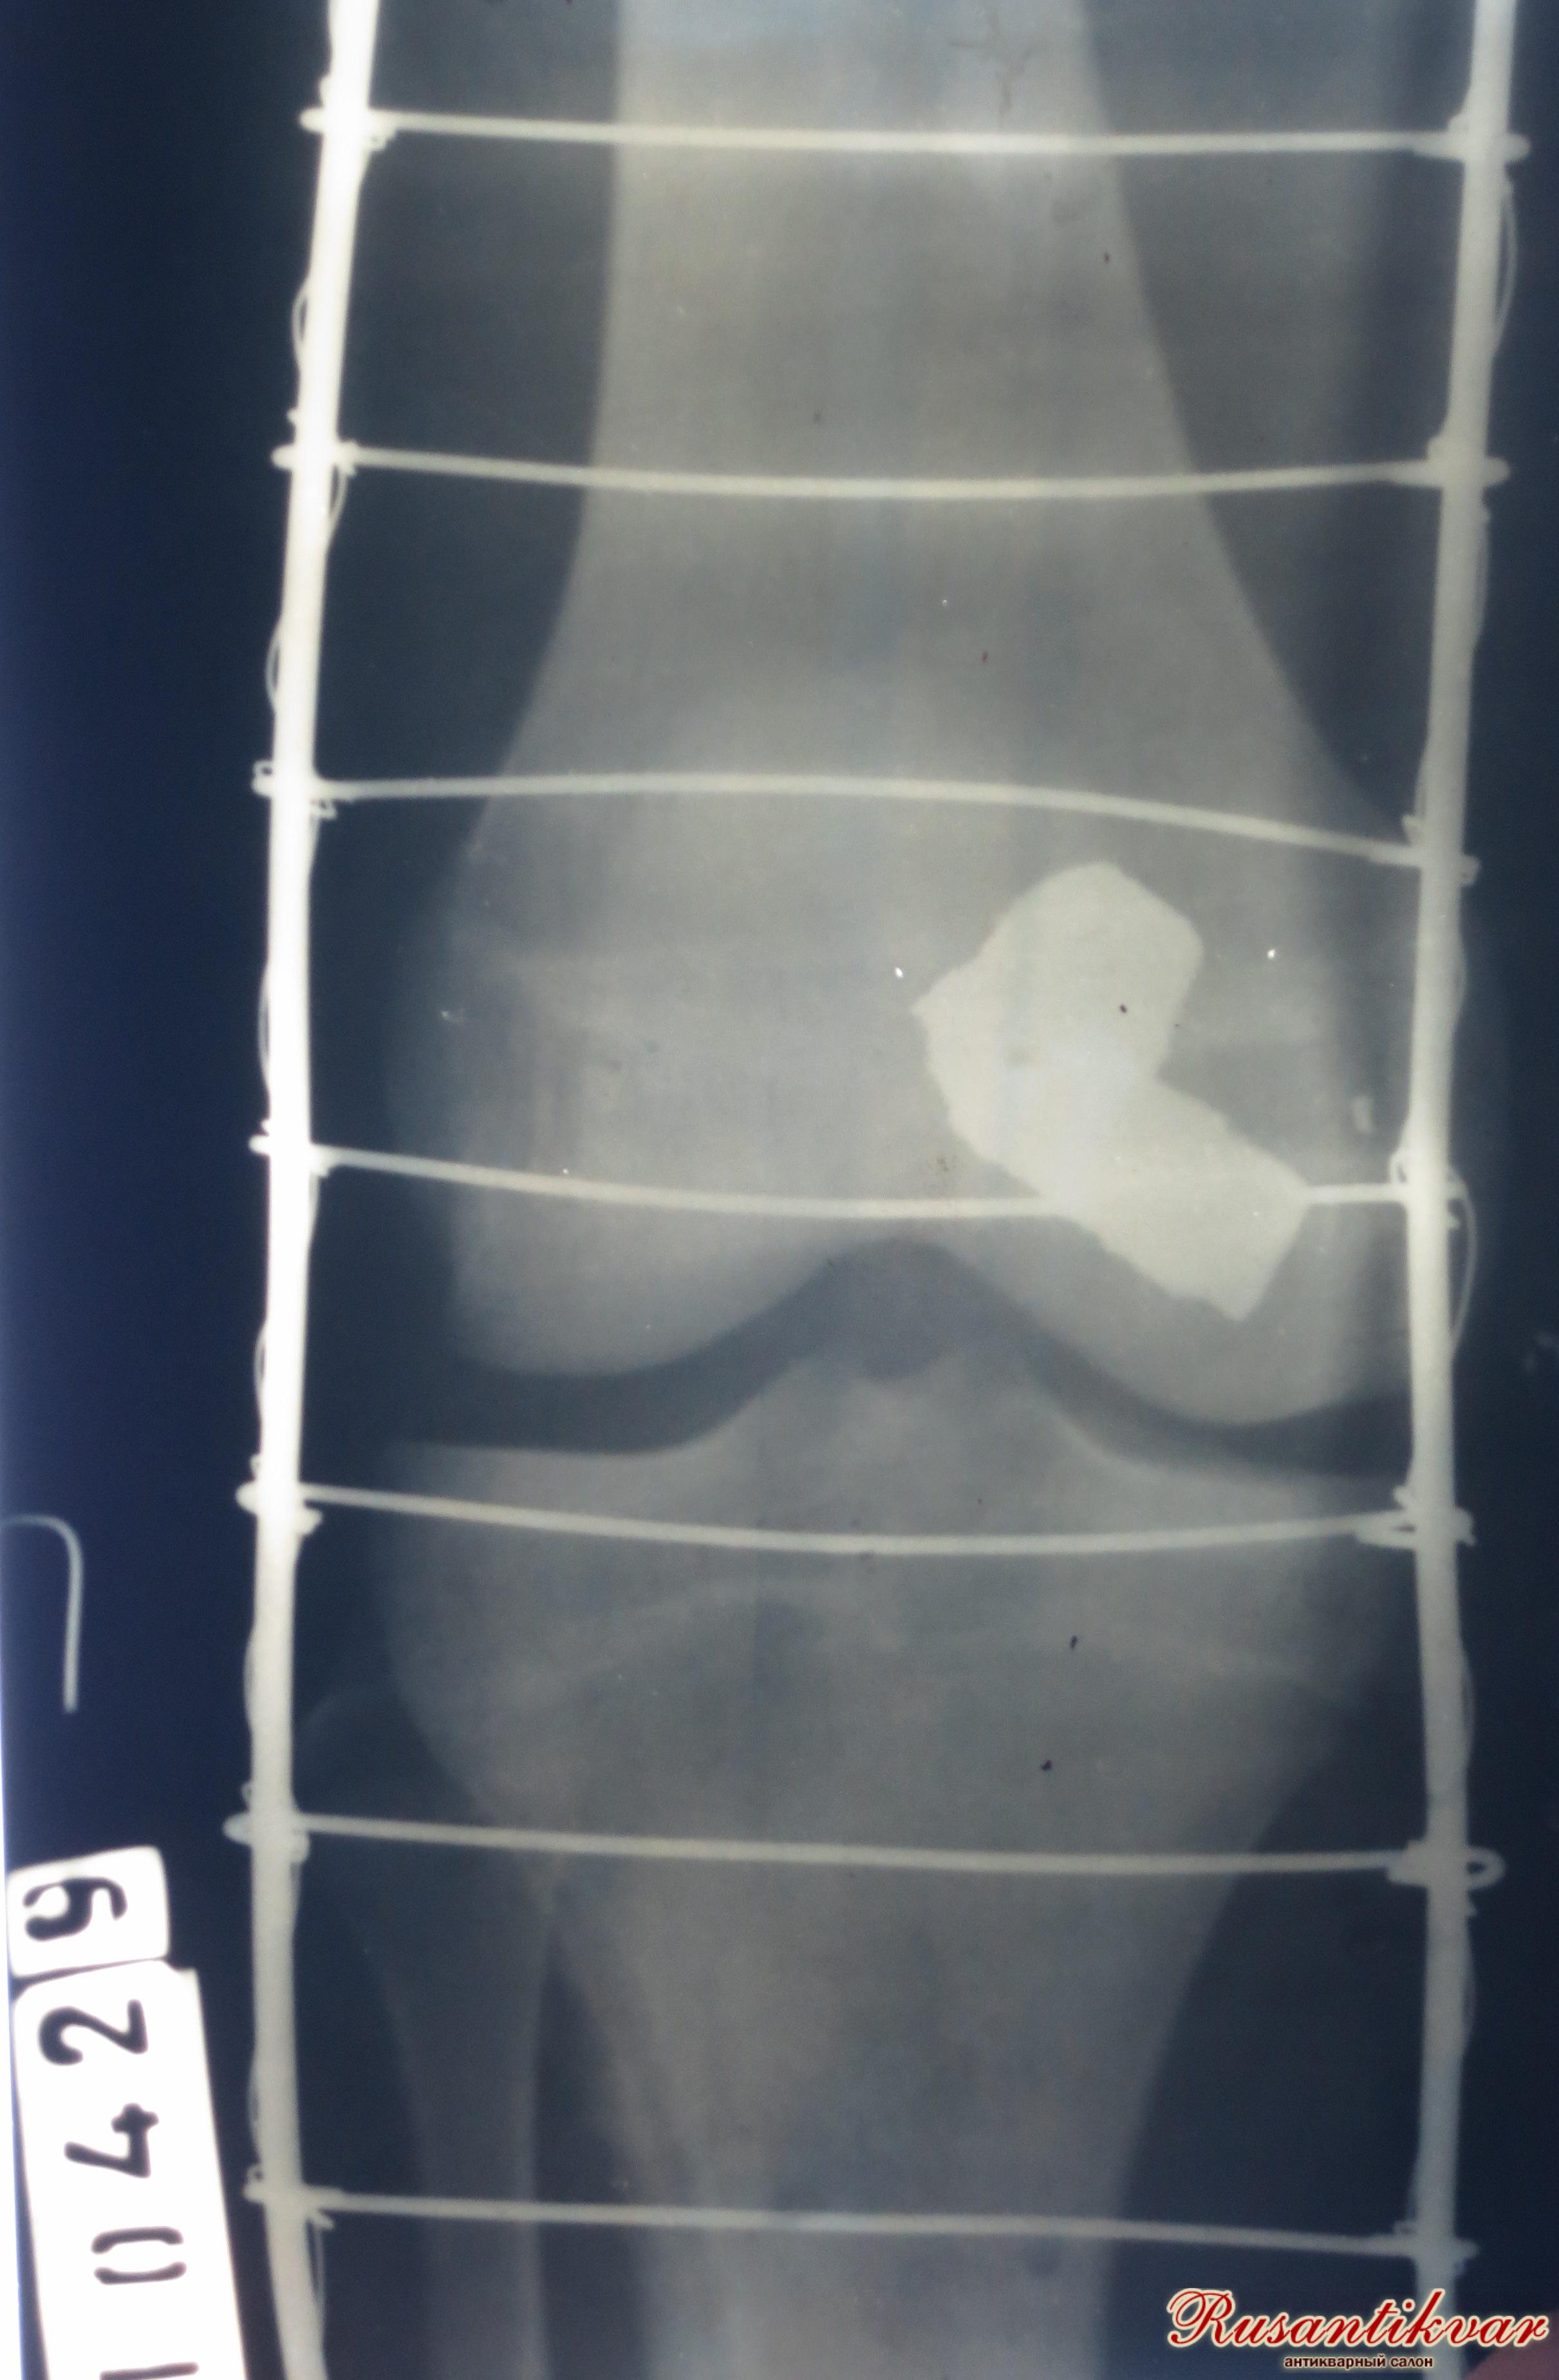

Предметный ряд рассматриваемой коллекции дополняет ещё один экспонат – рентгеновский снимок раненной шинированной ноги военнослужащего. На снимке чётко просматривается застрявший в бедренной кости осколок.

Рентгеновский снимок.